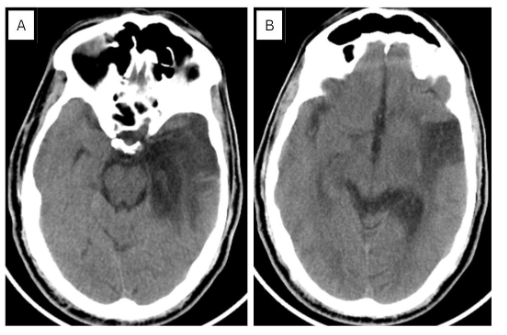

During that period, our list of potential diagnoses included herpesvirus reactivation, non-convulsive seizures, and other central nervous system infections. Consequently, acyclovir was initiated empirically. An emergency CT brain revealed a significant hypodense area in the left temporal region (see Figure 3), prompting a shift in the suspected diagnosis towards a potential ischemic stroke. The patient was admitted and started on antiplatelet therapy and statins. To detect signs of secondary CNS vasculitis due to herpesvirus a CT angiography was performed, but the results were normal. Re-analysis of cerebrospinal fluid (CSF) via PCR did not detect HSV DNA, leading to the discontinuation of acyclovir.

MRI was repeated and showed left temporal cortical/subcortical areas exhibiting encephalomalacia/gliosis (see Figure 4), with no evidence of restricted diffusion, thereby making stroke unlikely. An 18-channel awake EEG showed continuous focal epileptiform discharges over the left central parietal region, as quasi periodic discharges, over a background activity of moderate slowing (see Figure 5). This determination led to the diagnosis of postencephalitic non-convulsive status epilepticus. In light of this, the dosage of levetiracetam was escalated from 500mg BID to 1500mg BID. An EEG the following day showed resolution of status epilepticus but continued to display epileptiform discharges over the left fronto-central regions (Figure 6A). Consequently, lacosamide 200mg BID was introduced and EEG recorded 1 day later indicated the resolution of epileptiform discharges (Figure 6B). Upon discharge, the patient exhibited significant improvement in his clinical condition. Although he still experienced some baseline word-finding difficulty, his speech was notably more comprehensible. Additionally, he demonstrated no difficulty in responding to commands. It is important to note that the patient was an expatriate worker, and unfortunately there was loss to follow-up post-discharge.

In a retrospective review of patients with prior HSVE, postencephalitic epilepsy was noted in 45.5 % of the patients3. The predominant seizure patterns in postencephalitic epilepsy were unilateral temporal, bilateral temporal and multifocal or generalized with the majority of patients reporting an aura5. The high incidence of late unprovoked seizures following HSE may be due to the necrotizing nature of HSV-1 infection and involvement of the highly epileptogenic mesial temporal and basi-frontal cortices2. For example our patient’s repeat MRI scan showed the devastating impacts HSV can have on the brain including the profound atrophy of the left mesial temporal regions.